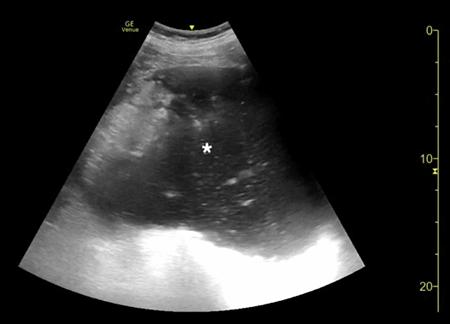

腹部床旁超声检查(POCUS)显示,胃部扩张并充满液体,高度疑似梗阻(图1,2)。

(图1 POCUS检查显示胃部膨胀充满液体[星号])

当怀疑有胃扭转时,选择初始的影像学检查非常重要,因为诊断延迟可能导致致命的并发症。CT检查高度可靠,主要有两种表现,即正常的胃窦幽门移行区和胃窦位置异常,诊断急性胃扭转的敏感性和特异性均为100%。POCUS是一种有效的非侵入性影像检查方式,主要用于床旁评估。此外,POCUS无辐射,并可根据临床情况随时进行重复检查。本例患者POCUS检查显示,胃部严重扩张,胃内容物分层,类似胃出口梗阻(GOO)的“黑白饼干”征象。POCUS还可以用来动态观察胃减压成功与否。